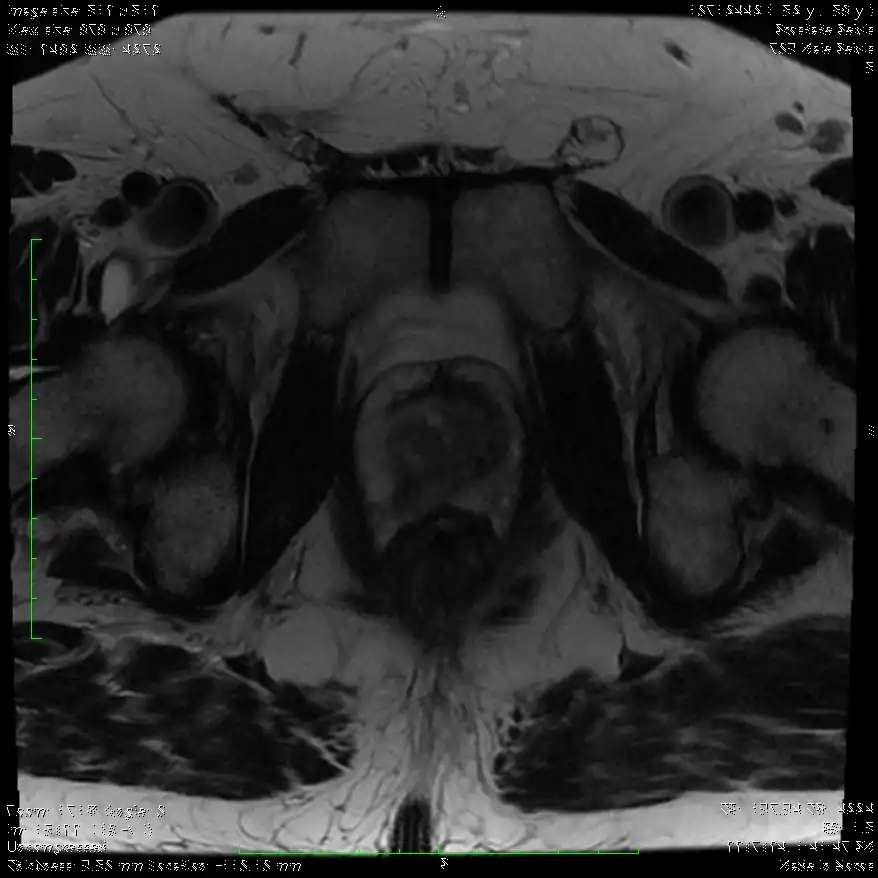

Η χρήση της πολυπαραμετρικής MRI στην διάγνωση του Καρκίνου του Προστάτη

Το 2018 ήταν η χρονιά που σε αρκετά έγκριτα περιοδικά (New England Journal of Medicine, European Urology, Lancet Oncology) δημοσιεύτηκαν μελέτες πάνω στο θέμα του καρκίνου του προστάτη. Οι μελέτες αυτές απέδειξαν την χρησιμότητα της πολυπαραμετρικής ΜRI στην αρχική διάγνωση. Κοινό συμπέρασμα σε όλες τις μελέτες ήταν η χρήση της πολυπαραμετρικής μαγνητικής τομογραφίας. Αυτό οδήγησε στην διάγνωση περισσότερων κλινικά σημαντικά καρκίνων.